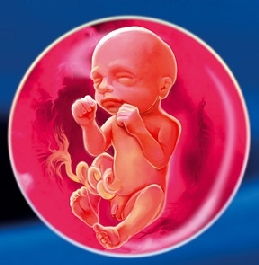

З радістю повідомляємо вам, що позаду вже більша частина шляху. Настала 22 акушерська тиждень вагітності, і плоду виповнилося цілих 20 тижнів від зачаття.

Особливості розвитку плода на 22 тижні вагітності плід

Ваш малюк вже неймовірно підріс, і в 22 тижні вагітності вага плода в середньому становить близько 430 г, а його зростання на цьому терміні досягає 28 см.